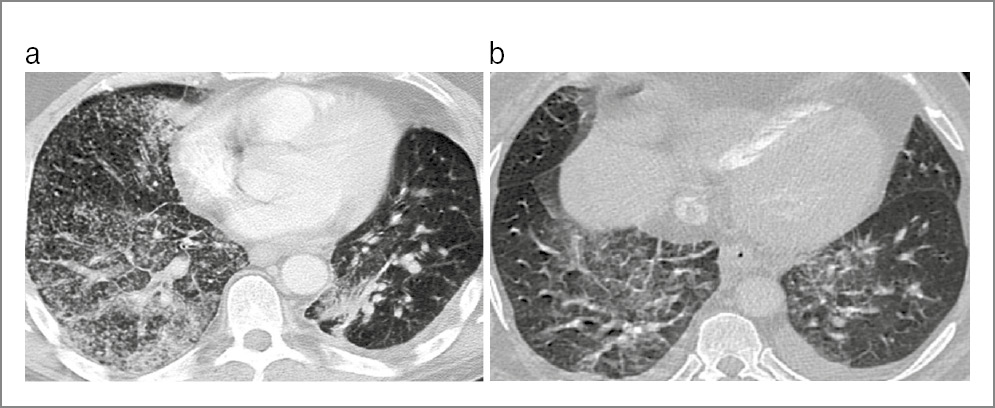

На КТ ОГК визуализировался комплекс одновременного сочетания 4 патологических синдромов: диссеминации, патологии плевры, усиления легочного рисунка и аденопатии. Синдром диссеминации представлен очагами разных размеров (от мелких до крупных) и интенсивности (от низкой до высокой), с тенденцией к слиянию и образованию инфильтратов негомогенного характера, с деструкцией легочной ткани и бронхогенным обсеменением. Синдром поражения плевры проявлялся уплотнением междолевой и париетальной плевры, а более чем у 1/2 пациентов – с развитием экссудативного плеврита или эмпиемы плевры. Синдром усиления и деформации легочного рисунка имел «сетчатый» характер вследствие развития интерстициальной пневмонии при лимфогематогенной диссеминации, с диффузным понижением прозрачности легочной ткани, развитием кистозно-дистрофических изменений и участками консолидации по типу «матового стекла». Синдром аденопатии представлен двусторонним увеличением внутригрудных лимфатических узлов с инфильтративными изменениями по периферии.

В то же время у пациентов групп 2А и 2Б чаще визуализировались инфильтраты, на фоне которых выявлялись просветы бронхов, преимущественно в нижних долях легких, с образованием мелких абсцессов, появлением выпота в плевральной полости, однако эти изменения также встречались и у больных групп 1А и 1Б.

Таким образом, у больных группы 1А с коморбидностью ДТЛ, КВП и ПЦП, 1Б с коморбидностью ДТЛ и ПЦП и без КВП, 2А с коморбидностью ДТЛ, КВП и ПЦП и 2Б с коморбидностью ДТЛ и ПКП и без КВП, с IVВ-стадией ВИЧ-инфекции, выраженным ИД, в фазе прогрессирования и в отсутствие АРВТ клиническая картина характеризуется синдромом интоксикации, общими воспалительными и респираторными проявлениями, практически одинакова и неспецифична, а особенности клинического течения коморбидного заболевания возможно определить только при выявлении конкретного возбудителя. В качестве примеров приведены КТ ОГК больных IVВ-стадией ВИЧ-инфекции с ИД, в фазе прогрессирования и в отсутствие АРВТ, иллюстрирующие сходство визуализации патологических изменений во всех группах (рис. 1, 2).

Рис. 2. КТ ОГК. Аксиальная проекция, режим легочного окна: a – пациент 39 лет с IVВ-стадией ВИЧ-инфекции с ИД, в фазе прогрессирования, без АРВТ и с верифицированной коморбидностью ДТЛ, КВП и ПКП; b – пациент 36 лет с IVВ-стадией ВИЧ-инфекции с ИД, в фазе прогрессирования, без АРВТ и с верифицированной коморбидностью ДТЛ и ПКП.

Как видно на рис. 1 и 2, на КТ ОГК визуализируются однотипные четыре синдрома: диссеминации, патологии плевры, усиления и деформации легочного рисунка с участками «матового стекла» и аденопатии.

Таким образом, на КТ ОГК у больных с коморбидностью туберкулеза органов дыхания (ТОД), КВП и ПЦП или ТОД и ПЦП и без КВП, IVВ-стадией ВИЧ-инфекции, в фазе прогрессирования и в отсутствие АРВТ с ИД визуализируются однотипные синдромы наслоения нескольких патологий, дифференцировать которые не представляется возможным, что требует своевременной диагностики с использованием микробиологических, молекулярно-генетических и иммунологических исследований для выявления M. tuberculosis, SARS-CoV-2, P. jiroveci, S. pneumoniae для адекватного своевременного этиологического лечения.